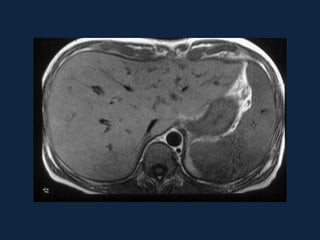

Abscesso Amebiano

►Lesão hipodensa, redonda ou oval, unilocular e

de localização periférica

►Septações internas (30%)

►Não há gás

►Contraste: realce periférico da lesão.

 Fase arterial